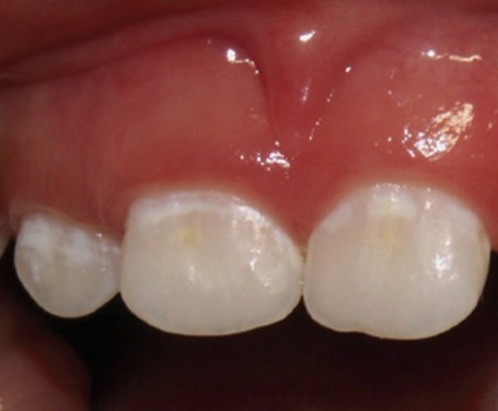

ちなみに

C0はこのような状態です。

歯の表面がちょっと白くなっています。エナメル質の表層が溶け始めているのです。

この状態でしたらフッ素塗布をして、

家でフッ素入り歯みがきでケアしてもらい経過観察します。

ケアがうまくいけば、虫歯は再石灰化されて詰める治療をせずに済みます。